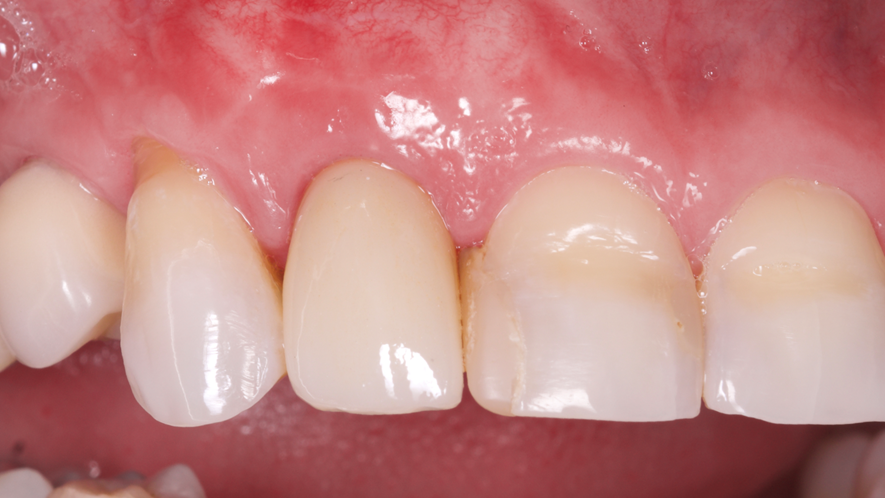

A restauração imediata pode apresentar algumas vantagens, como encurtar o tempo de tratamento, eliminar o uso de PPP ou provisórios ligados a dentes adjacentes, alta aceitação do paciente, eliminação da reabertura do implante e benefícios estéticos, sociais e psicológicos. A preservação do osso e das papilas dos dentes adjacentes ainda é citada como uma vantagem desta técnica5.

Os implantes Cone Morse foram criados com o intuito de minimizar problemas recorrentes na prática clínica odontológica, buscando maior segurança e longevidade das próteses fixas sobre os implantes e mostrando grandes resultados na estética6. O conceito Cone Morse apresenta vantagens protéticas significativas em comparação aos implantes hexágonos, principalmente em elementos unitários anteriores, tendo em vista que a longevidade da estética gengival é de suma importância, demonstrando qualidades clínicas, biológicas e biomecânicas superiores7.

Este trabalho tem como objetivo relatar um caso clínico de exodontia minimamente invasiva de um incisivo lateral superior com fratura radicular, realizando implante imediato em alvéolo pós-extração, enxerto de tecido conjuntivo subepitelial e osso bovino liofilizado para preenchimento de GAP, prontamente à instalação de pilar reto e provisório imediato.